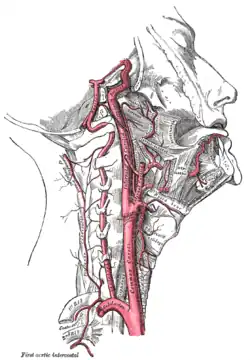

Die in der Neurologie wichtigsten Organsysteme sind das Zentralnervensystem (also Gehirn und Rückenmark), seine Umgebungsstrukturen und Blutgefäße. Dazu kommt das periphere Nervensystem und die Muskulatur, einschließlich der Verbindungsstrukturen zwischen beiden. In Deutschland ist die Neurologie um 1845 mit Moritz Heinrich Romberg als ein Teilgebiet aus der Inneren Medizin hervorgegangen. In den USA, in Großbritannien, Russland und anderen Staaten dagegen hatte sich die Neurologie gleich als eigenständiges Fach entwickelt.[1]

Die hirnversorgenden Gefäße können mittels Ultraschall (extrakranielle und transkranielle Doppler- und Duplexuntersuchungen) und invasiver Verfahren (z. B. Angiografie) untersucht werden.

Eine 62 Jahre alte Frau wird mit einer plötzlich aufgetretenen Gangunsicherheit in die Notaufnahme gebracht. Sie klagt außerdem über eine neu aufgetretene „Heiserkeit“. Die Patientin ist Diabetikerin und leidet an Bluthochdruck. Sie berichtet, sie habe sich vor ziemlich genau einer Stunde ihr Insulin gespritzt, ihre Blutdruckmedikamente eingenommen und danach sei es ihr merkwürdig gewesen und sie sei beim Aufstehen gestürzt. Angehörige brachten sie dann sogleich in die Notaufnahme. Eine Gangprüfung zeigt, dass die Patientin nur mit Hilfe stehen kann, obgleich ihre Kraft in den Beinen unbeeinträchtigt ist. Die Inspektion zeigt, dass ihr rechtes Oberlid leicht herabhängt. Als der Neurologe ihr einen Spiegel vorhält, erkennt sie, dass ihr rechtes Auge „schief“ ist. Die Untersuchung zeigt ein aufgehobenes Temperaturempfinden im Bereich des linken Armes. Eine CCT des Gehirnschädels zeigt keine auffälligen Veränderungen. Bei einer Dopplersonographie der extrakraniellen hirnversorgenden Gefäße lässt sich die Vertebralarterie rechts nicht darstellen. Die Verdachtsdiagnose lautet Wallenberg-Syndrom infolge eines Hirninfarkts der dorsolateralen Medulla oblongata im Versorgungsgebiet der Arteria cerebelli inferior posterior rechts aufgrund eines Verschlusses der Vertebralarterie rechts.

Die ätiologische Diagnose im Falle der älteren Dame ist vermutlich ein embolischer Verschluss einer Hirnarterie aufgrund von arteriosklerotischen Veränderungen in der vorgeschalteten Strombahn mit der Folge eines ischämischen Infarktes des durch das Gefäß ursprünglich versorgten Gehirnareals. Möglich wäre auch ein sogenannter Grenzzonen-Infarkt aufgrund einer durch Arteriosklerose verursachten Lumenminderung (Stenose) der vorgeschalteten Gefäße.

Fallbeispiel VI: Ein junger Mann mit einem Hirninfarkt

Ein etwa 35 Jahre alter Mann wird mit den Zeichen eines akuten ischämischen Hirninfarktes in die Klinik eingeliefert. Nach Angaben von Arbeitskollegen sei er gestürzt, klagte dann plötzlich über Unwohlsein und sprach undeutlich. In der Aufnahmesituation zeigt der Patient eine Arm- und Gesichtslähmung rechts, er ist benommen und aphasisch. Das Ereignis ist weniger als 45 min alt. Eine CCT-Untersuchung zeigt in dieser Phase noch keine Frühzeichen eines Hirninfarktes, wird aber zum Ausschluss einer Hirnblutung durchgeführt. Eine doppler- und duplexsonographische Untersuchung der Halsgefäße zeigt Hinweise für einen Verschluss der Arteria carotis interna (ACI) links. Die Diagnose lautet: Verschluss der ACI links mit ischämischem Hirninfarkt im Mediastromgebiet links. Es wird eine Lysetherapie eingeleitet. Lähmung und Sprachstörung bilden sich völlig zurück. Dopplersonographisch zeigt sich weiterhin eine hochgradige Strömungsbehinderung der ACI links. Der Patient hat allerdings keine Gefäßrisikofaktoren. Aus diesem Grund wird die Anamnese noch einmal überprüft. Dabei berichtet der Patient, er sei kurz vor dem Ereignis gestürzt und sehr unglücklich mit der linken Halsseite gegen eine Tischkante gefallen. Die Verdachtsdiagnose einer Dissektion der Arteria carotis interna wird durch eine Kernspintomographie der Halsgefäße bestätigt.